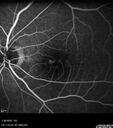

Peripapillary CNVM No Treatment20 views85 year old with peripapillary CNVM watched for many years.